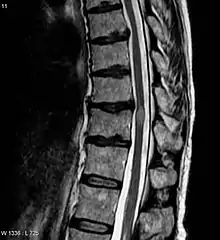

| An MRI showing a transverse myelitis lesion, which is lighter, oval shape at center-right. The patient recovered 3 months later. | |